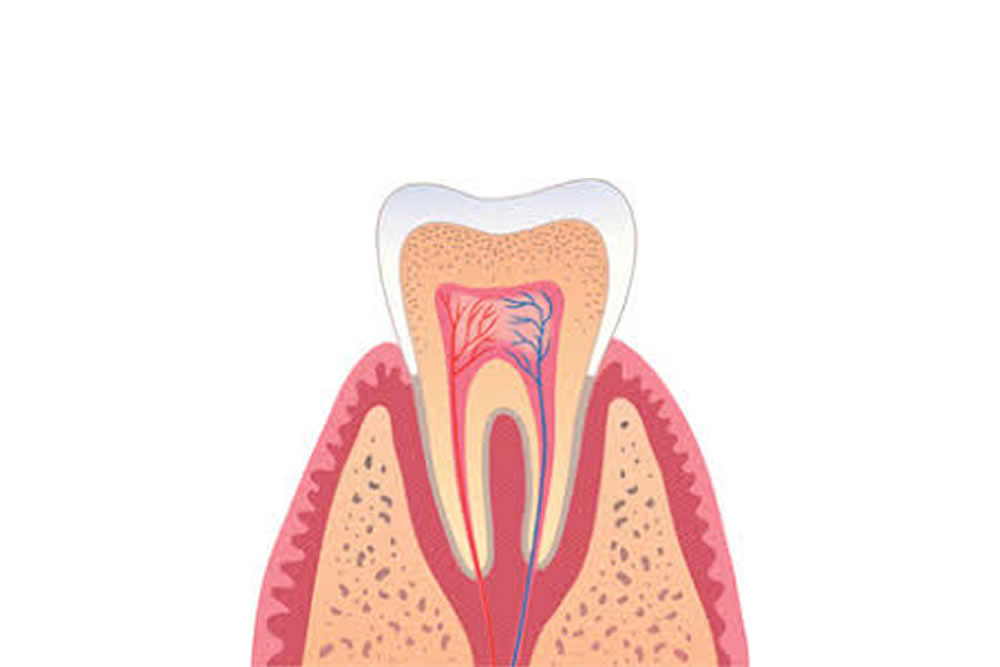

マイクロスコープ

歯科顕微鏡とも呼ばれ、視野を30倍まで拡大する事が可能な精密機器です。拡大する事で細部に対して、精度の高い処置が行えるようになります。

歯科顕微鏡とも呼ばれ、視野を30倍まで拡大する事が可能な精密機器です。拡大する事で細部に対して、精度の高い処置が行えるようになります。

当院では、根管治療や歯周病をはじめ、様々な治療に用いて精密な処置を行っています。

条件が揃えば、通常抜歯となる歯でも保存することが可能です

肉眼の約10倍拡大図下での治療図

肉眼の約20倍拡大図下での治療図

肉眼の約30倍拡大図下での治療図